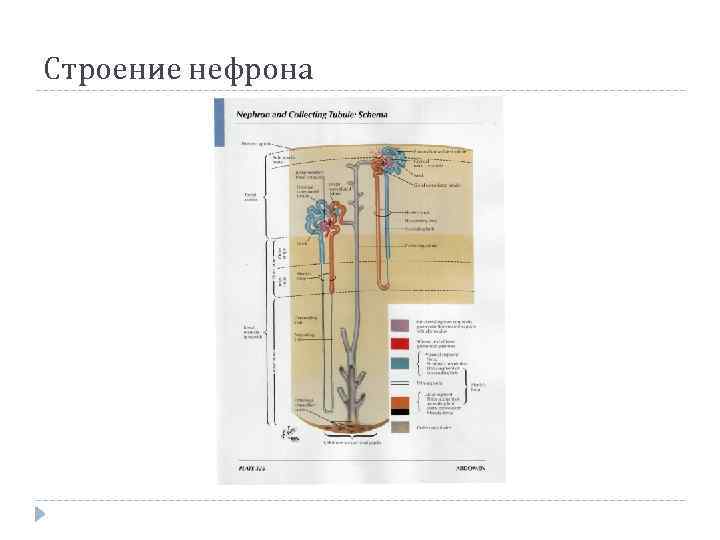

Структурно-функциональной единицей почки является НЕФРОН Почечное тельце (Мальпигиево) Клубочек капилляров Капсула клубочка (Боумена – Шумлянского) Канальцы нефрона: Проксимальный извитой кааналец Петля нефрона (Генле) Дистальный извитой каналец Собирательные трубочки

Структурно-функциональной единицей почки является НЕФРОН Почечное тельце (Мальпигиево) Клубочек капилляров Капсула клубочка (Боумена – Шумлянского) Канальцы нефрона: Проксимальный извитой кааналец Петля нефрона (Генле) Дистальный извитой каналец Собирательные трубочки

Строение нефрона

Строение нефрона